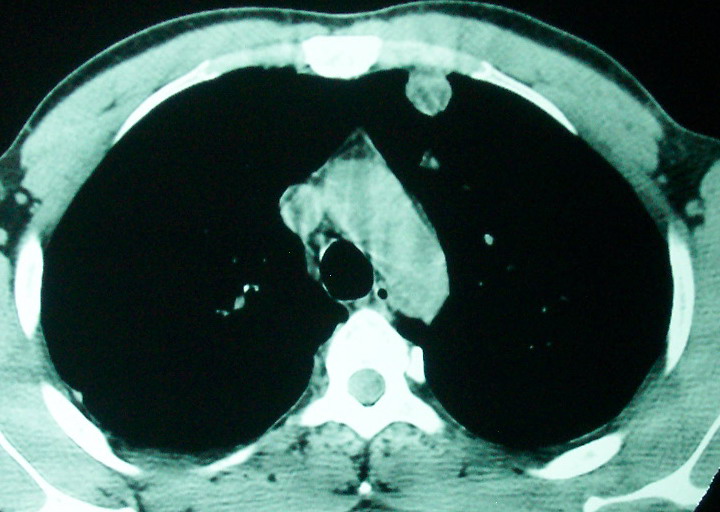

m      37y      发热   咳脓痰月余      ct肺脓肿但住院抗炎治疗后双肺内结节不知该如何解释

治疗后见左肺下野病灶较前缩小但双肺内结节影似无变化请较各位老师该如何下结论    治疗前wbc14.5 治疗后wbc 11.0

空洞内可见小结节样密度影考虑合并真菌感染

我看是不是可以两元化来解释,左肺下叶还是肺脓疡,而其余病灶考虑肺癌伴肺内转移,我看右肺上叶尖段病灶可见明显毛刺改变为原发病灶.

1、左下肺鳞癌伴两肺及纵隔淋巴结转移;

2、两上肺支扩伴慢性炎症。

左下肺病灶除了明显的厚壁空洞 气液平外,明显见壁结节,另两肺多发小结节,综合考虑:左下肺周围性肺癌伴肺内转移.

除了肺内多发结节和左肺下叶的浓疡病灶,还应注意满肺散在的小结节影,还有右上肺前段支气管内膜不光整这些细节,结合病史,肺内多发结节应考虑结核性肉芽!

如果你仔细的同层面对比,你会发现所有的病灶均有比较明显的吸收、缩小。病变的形态,特别是脓肿的形态、壁的厚薄、内壁均有很大的变化,均在往好的方面发展。与临床症状、血像均符合,治疗效果比较显著,就是肺脓肿并双肺的化脓性炎症灶。